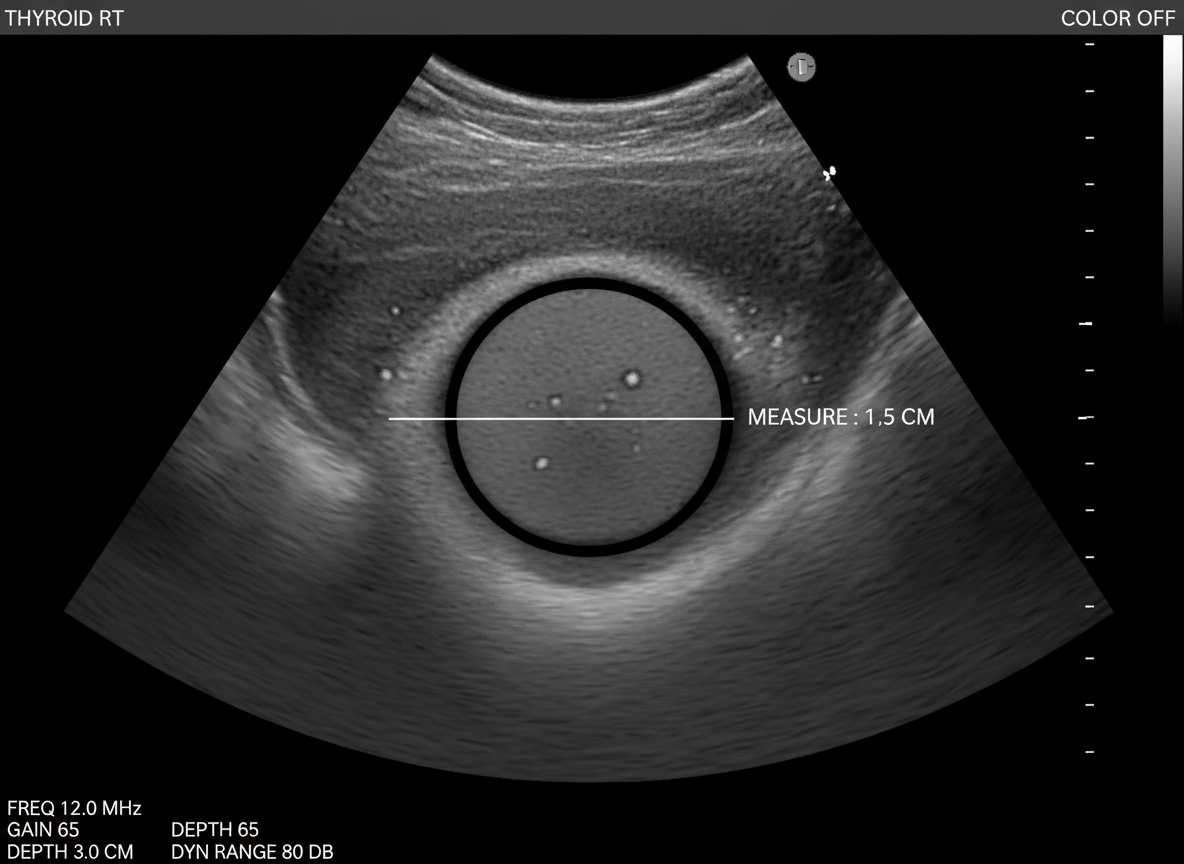

가장 기본적이고 중요한 검사는 갑상선 초음파 검사예요.

목 주변의 갑상선을 영상으로 자세히 살펴보면서

결절의 크기, 모양, 위치 등을 확인하는 검사죠.

초음파에서 이상 소견이 발견되면